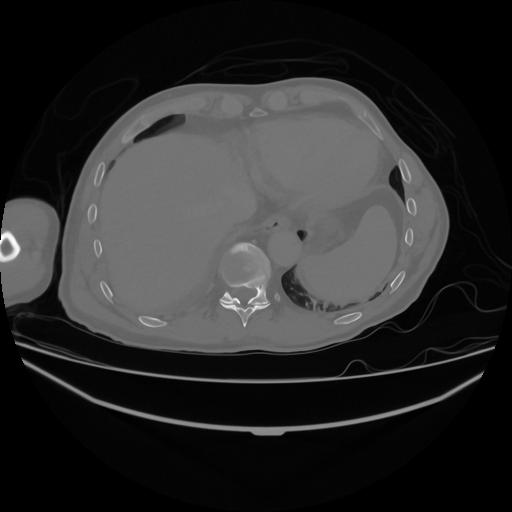

5 CUERPO,CE,Vol,1.0,CUERPO,,